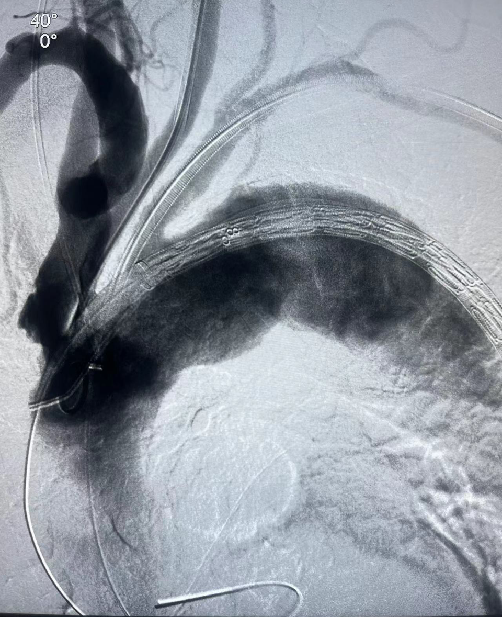

患者男性,78岁,胸主动脉瘤,采用双开窗技术(LSA+LCCA)重建分支。Futhrough系统在直径较小的血管中(成角小、行程长)实现精准穿刺,术后12个月随访显示支架通畅,无内漏或移位。

case 2